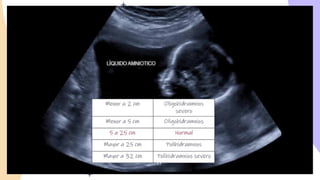

Maxima columna vertical

Se realiza midiendo la máxima columna vertical

de liquido de partes fetales y de cordón

umbilical.

Indice de liquido amniòtico

Es el valor obtenido a partir de la suma de las

máximas columnas verticales de liquido amniótico

libre de las partes detales y cordón umbilical, en cada

uno de los 4 cuadrantes que se delimitan por

intersección de dos líneas pediculares en el abdomen

materno: la línea media longitudinal con la línea

trasversal media entre las sínfisis publica y el fondo

uterino.

El transductor e coloca en posición sagital y lo mas

perpendicular posible al suelo